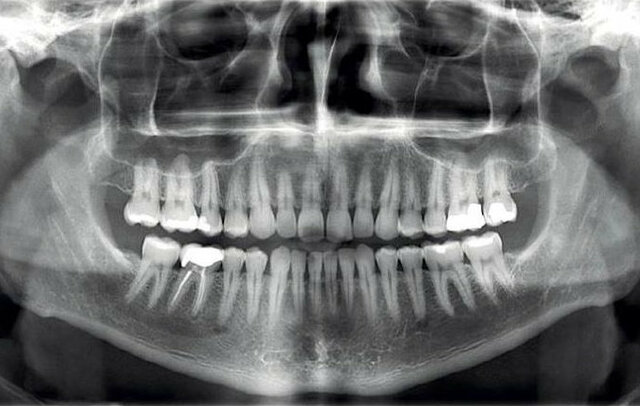

• Ortopantomografía Convencional

Ortopantomografía Convencional

El primer trabajo experimental fue llevado a cabo en Japón en 1933, pero fue el profesor Paa-tero de Finlandia, quien tuvo éxito en producir la aplicación práctica de esta técnica en la Universidad de Washington en Seattle entre 1950-1951, donde se desarrolló una máquina prototipo.